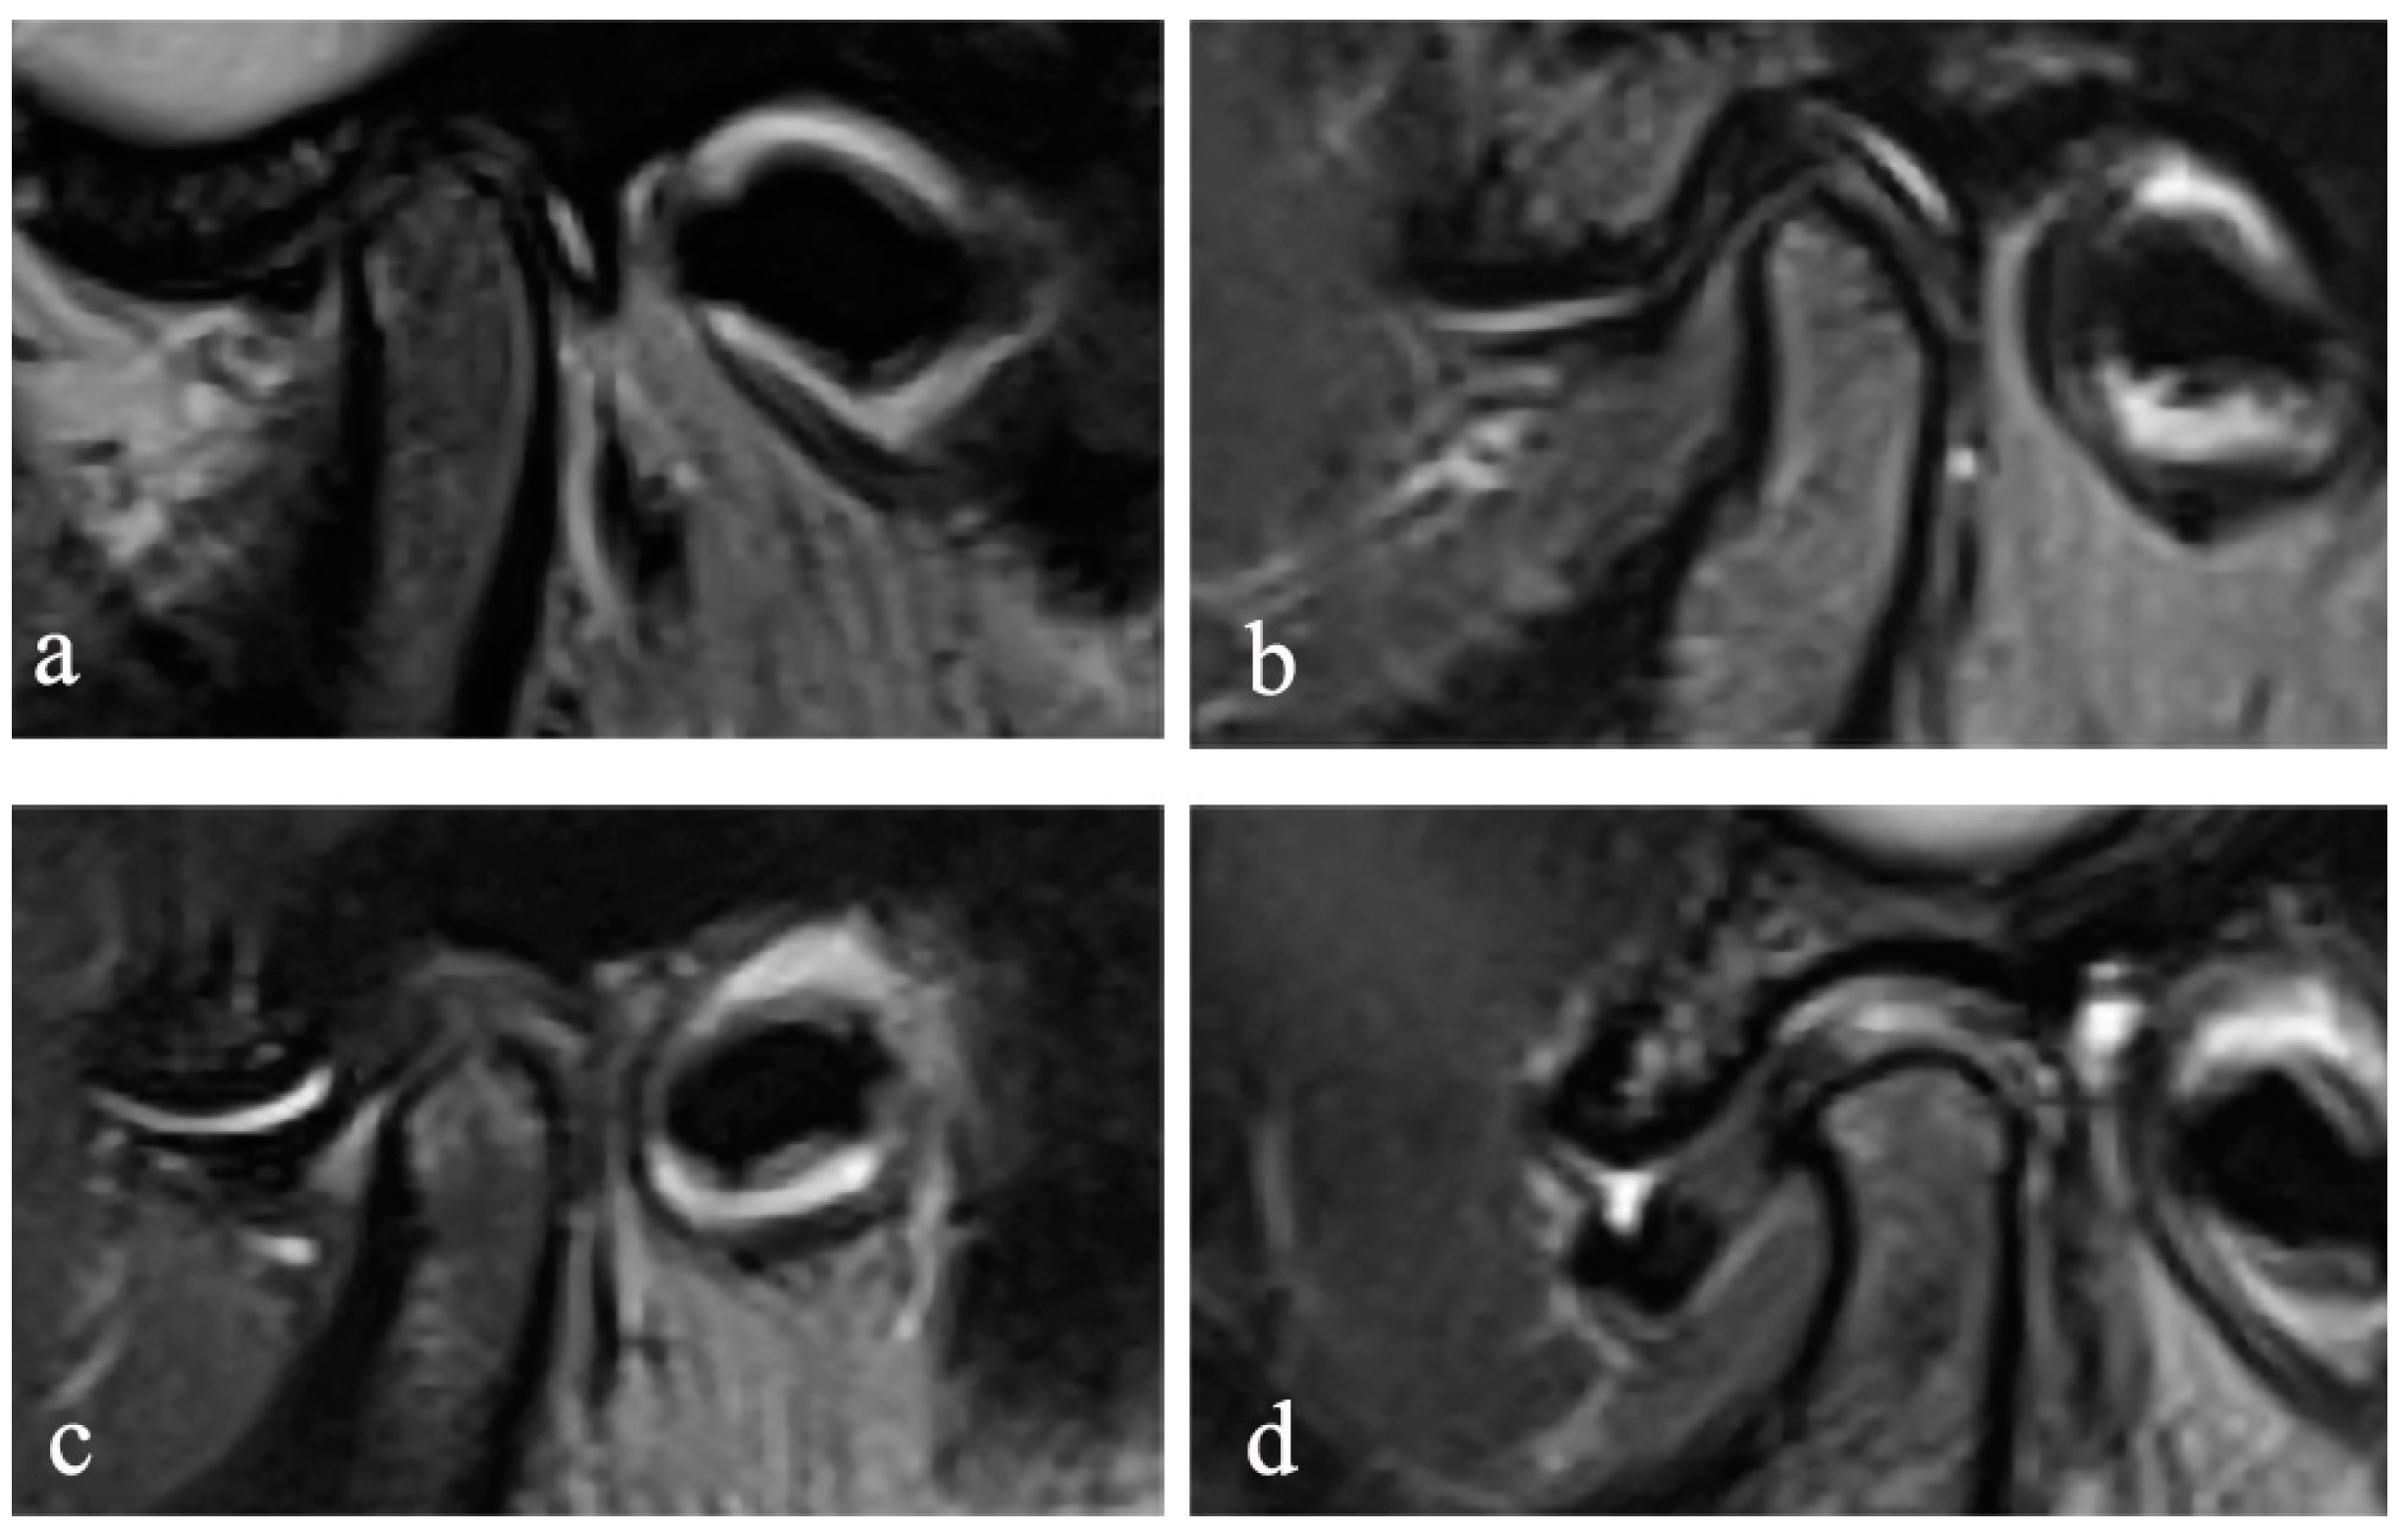

2.3. Assessment of the MR and CBCT Images

The MR images were randomly numbered and evaluated by using Radiant 5.0.0 software (Poznan, Poland) on the same laptop, and the information of the subjects, including the disc position, disc configuration, and JE, were hidden. In the closed and open mouth positions, the maximum section of the articular disc shown on the oblique sagittal PDW image was selected to evaluate the configuration of the disc. According to the method proposed by Raweewan [17], the disc configuration was divided into four types: biconcave, biplanar, convex, and folded (Figure 1). The biplanar, convex, and folded types were defined as deformation. Combined with the oblique sagittal and the oblique coronal PDW images, the position of the disc was described by Tasaki’s method [18]. Furthermore, JE was classified into 0–3 levels (Figure 2) on the oblique sagittal T2W images in the closed mouth position, according to the criteria proposed by Segami et al. [19]. The degree of JE was dichotomized into two groups for intra-group statistical analysis: JE-, grade 0 or 1, and JE+, grade 2 or 3.

Figure 2. Joint effusion. Sagittal T2-weighted image MRI showing: (a) no fluid signal, (b) dots or lines of bright signal, (c) bands of bright signal, and (d) pooling of bright signal on the TMJ.